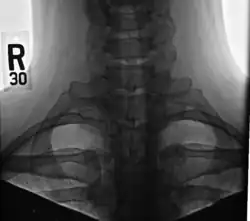

À l'imagerie, les côtes cervicales peuvent être distinguées car leurs apophyses transverses sont dirigées inférolatéralement, alors que celles du rachis thoracique adjacent sont dirigées antérolatéralement[7].